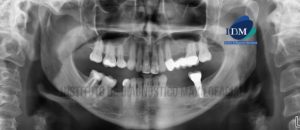

Paciente masculino de 64 años acude al Instituto de Diagnóstico Maxilofacial para la evaluación imagenológica de control. A la evaluación de la radiografía panorámica se